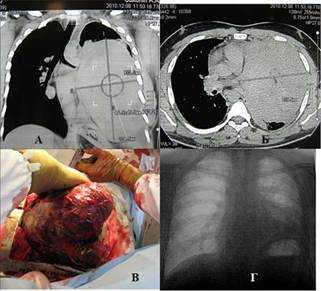

Наблюдение 2. Мужчина 24 лет. Строитель. В течение 2 недель стал ощущать слабость, боль в груди, Т >38o, одышку. До этого считал себя здоровым, работал. На КТ определяется массивное солидное гомогенное образование, занимающее практически весь левый гемиторакс и смещающее средостение вправо (рис. 2 а, б). При УЗИ левой плевральной полости определяется жидкость. При плевральной пункции удалено около 2,5 л серозного экссудата. Трансторакальная игловая биопсия: опухолевая ткань, наиболее вероятно герминогенной природы с участками некроза. Операция: полная продольная торакотомия. Опухоль с большими техническими трудностями из-за плотных сращений отделена от грудной стенки. Выделение сопровождалось значительным диффузным кровотечением. Легкое в ателектазе, инвазии его нет. Множественные сосудистые ножки, исходящие из переднего средостения, лигированы и пересечены. Опухоль удалена. Масса опухоли 2,8 кг (рис. 2в). Продолжающееся фибринолизное кровотечение в послеоперационном периоде купировано, кровопотеря возмещена. Дальнейший послеоперационный период без осложнений. При выписке левое легкое полностью расправлено (рис. 2г). Морфологически: незрелая тератома. Далее химиотерапия в режиме ВЕР 4 цикла. Смерть от прогрессирования опухолевого процесса 2 года спустя.

Рис. 2. Наблюдение 2: а, б) компьютерные томограммы пациента, в) полная продольная стернотомия, извлечение препарата, г) обзорная рентгенограмма пациента спустя 7 дней после операции